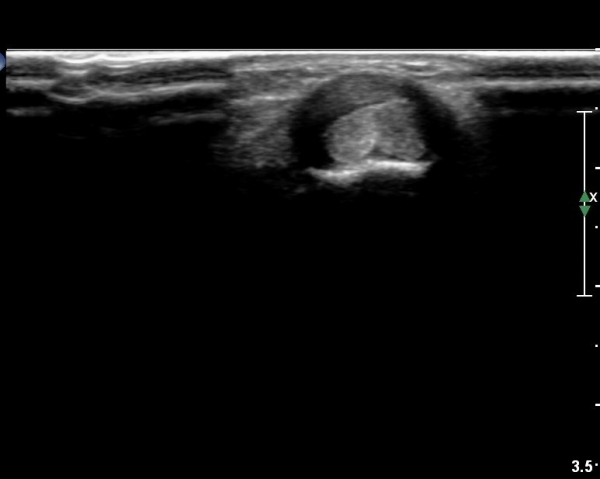

¼Õ¸ñ µî Áß¾Ó¿¡¼­ ¼Õ°¡¶ô ½ÅÀü°Ç Á¾´Ü¸é °Ë»ç¿¡¼­ ƯÀÌ ¼Ò°ßÀ» º¸ÀÌÁö ¾Ê´Â´Ù(»çÁø 1)